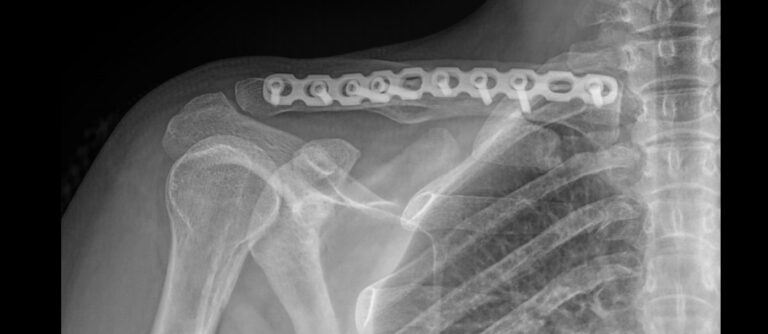

Ключица вместе с лопаткой составляет пояс верхней конечности и участвует в присоединении руки к грудной клетке. Ключица тонкая и хрупкая, но благодаря своей изогнутой форме отлично справляется со своей функцией. Перелом может произойти при сильном прямом ударе или падении. Во многих случаях перелому сопутствует вывих в акромиально-ключичном суставе. Реже наблюдаются дистрофические поражения сустава или онкология. Факторами риска выступают эндокринные нарушения, прием гормональных препаратов в лечебных и спортивных целях, а также возраст.

Рентгенография используется в качестве первичного  исследования при любых патологиях ключицы. Классическая рентгеновская съемка неинвазивная, безболезненная и простая в выполнении для пациента. Обычно такого исследования достаточно для подтверждения диагноза или отслеживания лечебного процесса. Что касается ионизирующего излучения, дозы, излучаемые  современными аппаратами настолько малы, что не набирают и минимально допустимых показателей даже при выполнении серии снимков.

Что покажет рентген ключицы

• Состояние мягких тканей;

• Наличие перелома, в том числе заживающего или уже зажившего, его местоположение;

• Наличие вывиха;

• Состояние суставной щели акромиально-ключичного сустава и грудино-ключичного сочленения;

• Изменения в костной ткани ключицы.